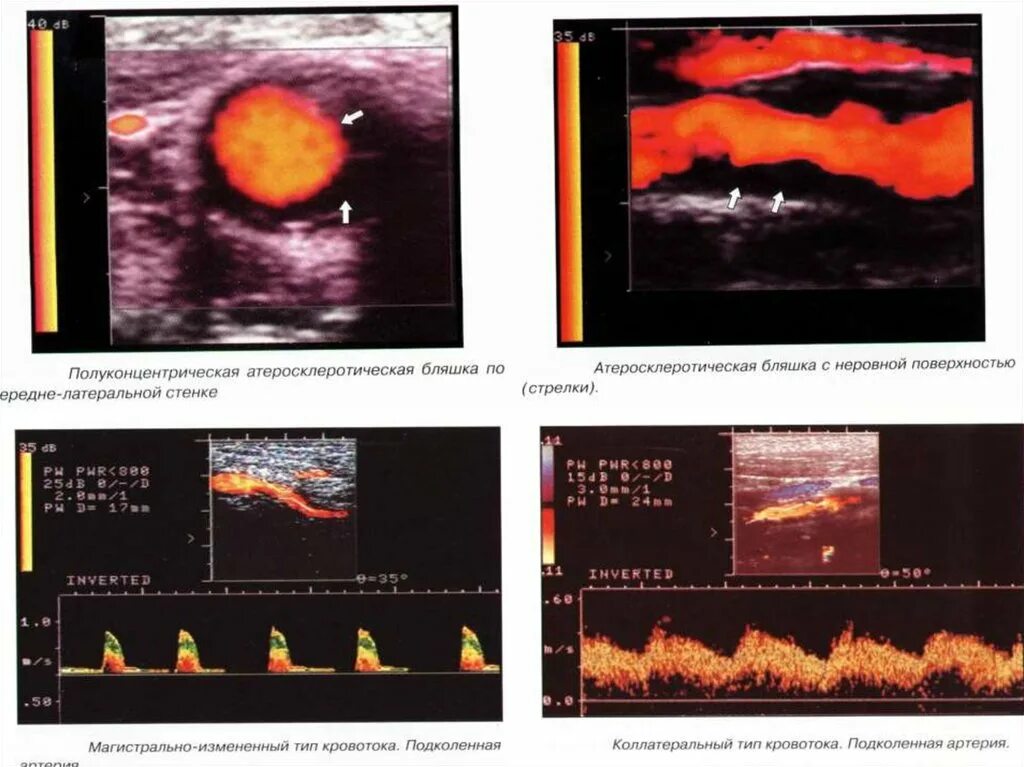

Атеросклероз на узи